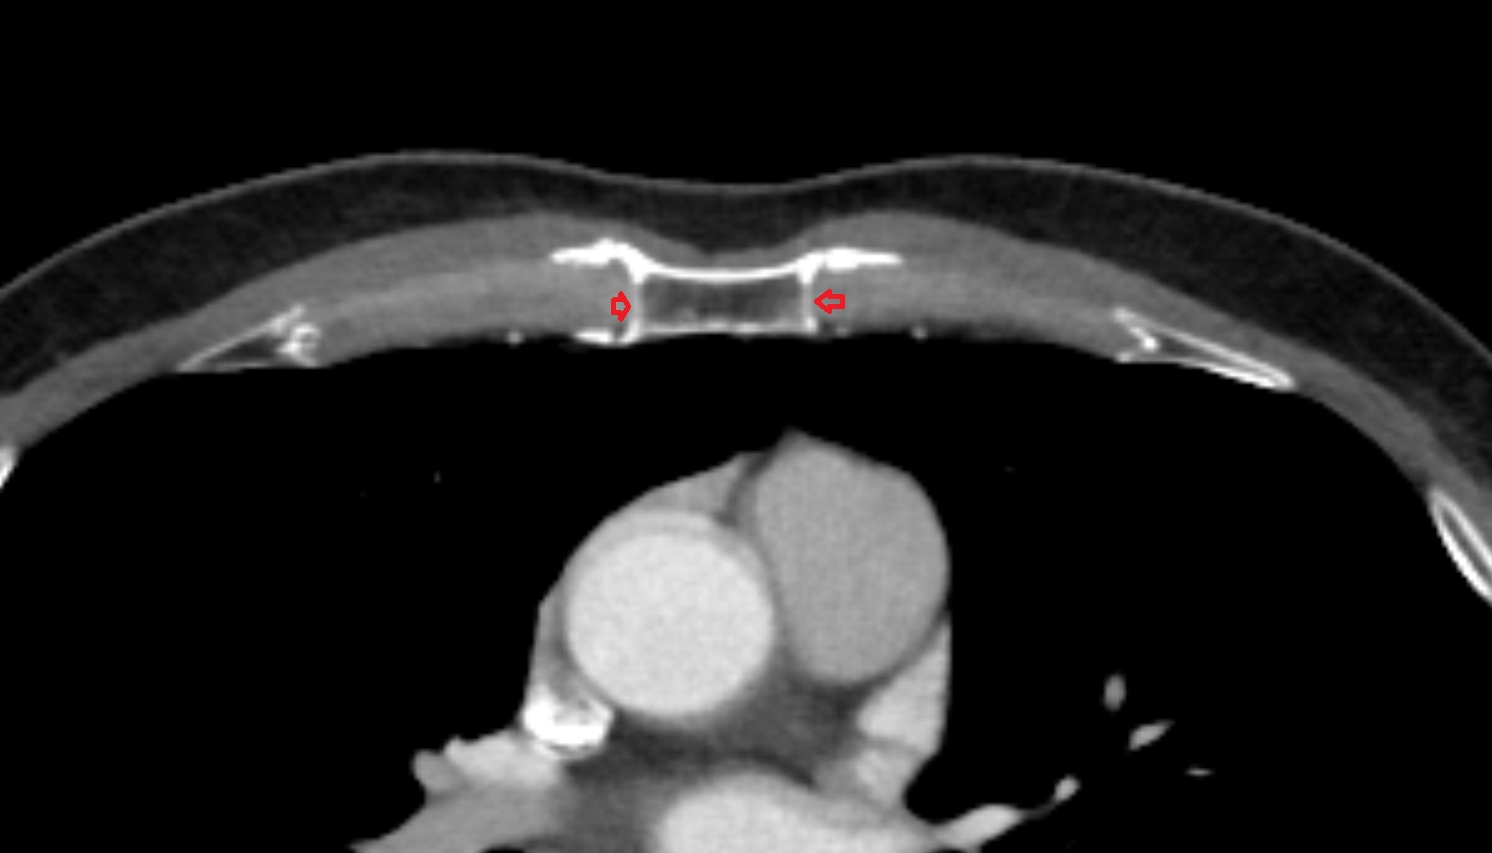

- Sternocostal joint

- Sternocostal synchondrosis of first rib

- Costochondral joints

- Costal cartilages